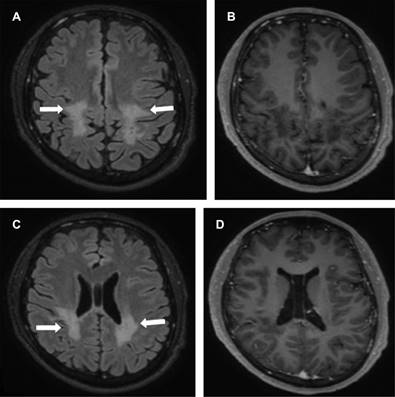

Masculino de 17 años con dos semanas de febrícula, cefalea, ataxia, disminución de agudeza visual de predominio derecho, temblor, fuerza disminuida en extremidades. Laboratoriales: leucocitos 10,100/mm3 con 75%N, proteína C reactiva (PCR) 41.2 mg/L, ELISA VIH negativo, tóxicos en orina negativos. Punción lumbar: leucocitos 70/μL (92% mononucleares), glucosa 68 mg/dL, sugerentes de EMDA, se realizó resonancia de ingreso (Figura 1); se descartó EM por negatividad de bandas oligoclonales IgG específicas, con positividad para anticuerpos anti-MOG mediante EBC. El tratamiento agudo se realizó con metilprednisolona intravenosa a dosis altas con discreta mejoría, en resonancia control presentó compromiso de médula espinal, así como de nervios ópticos (Figura 2); se adicionaron inmunoglobulinas, ocho meses después presentó mejoría sintomática. En resonancia de seguimiento para valoración de tratamiento con disminución de lesiones sin realce de las mismas (Figura 3).